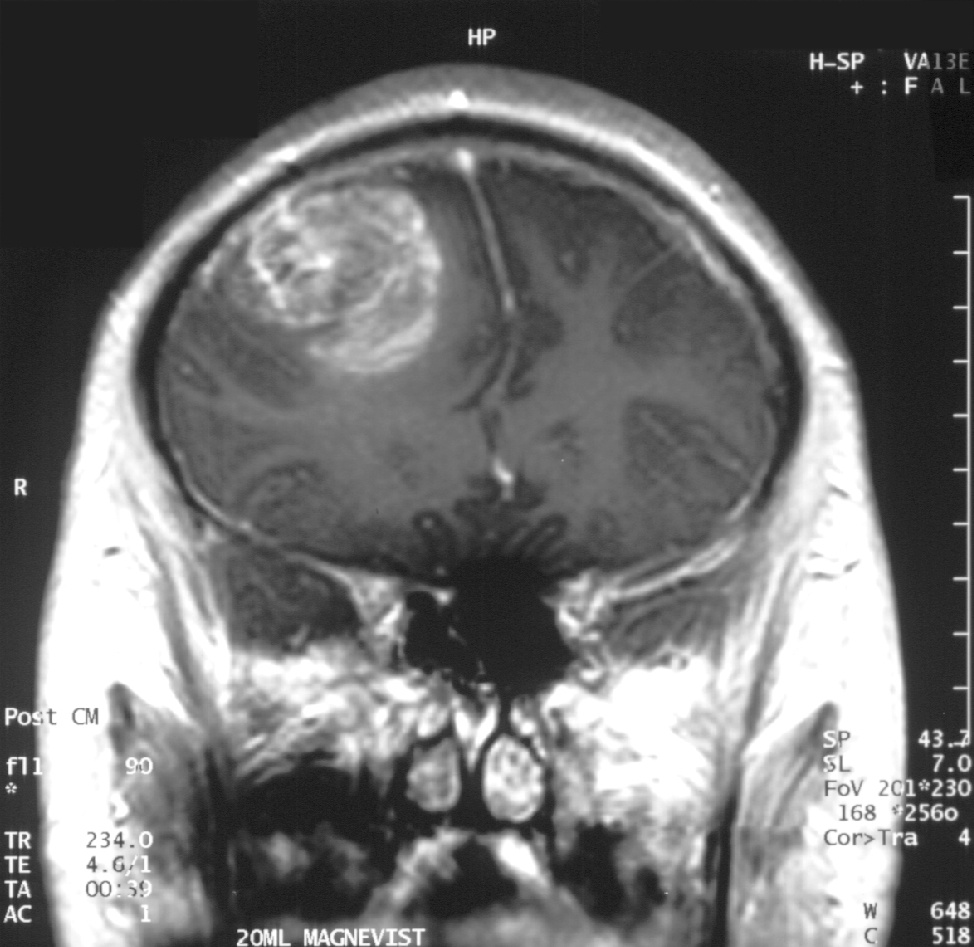

Глиобластома или же мультиформная глиобластома (последний термин уже не используется в официальных обозначениях ВОЗ, но опухоль и теперь часто так называют) – это высокоуровневая глиома (степень IV), самая злокачественная форма астроцитомы. Таким образом, мультиформная глиобластома, глиобластома – это синоним обозначения «глиома степени IV». Гистологически глиобластому отличает наличие участков некроза (погибших клеток) и активный рост кровеносных сосудов вокруг опухоли. Образования четвертой степени – это всегда быстро растущие, агрессивные и очень злокачественные опухоли.